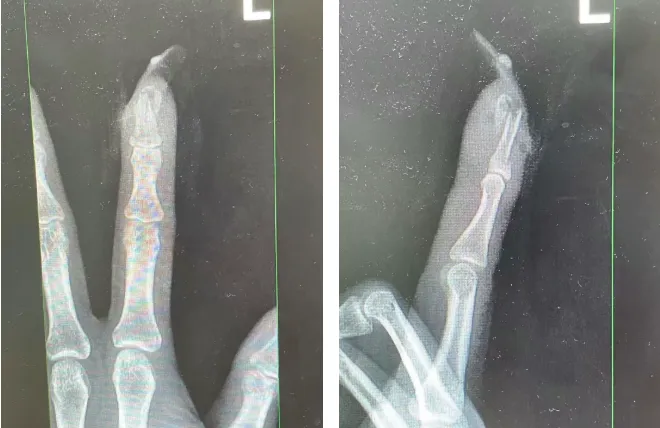

经检查

王女士指甲断裂

部分甲床外露

医生表示如果没有美甲

伤害不会这么严重

698579433882e.png.webp

王女士受伤手指的X光影像。图源:杭州市临平区中西医结合医院